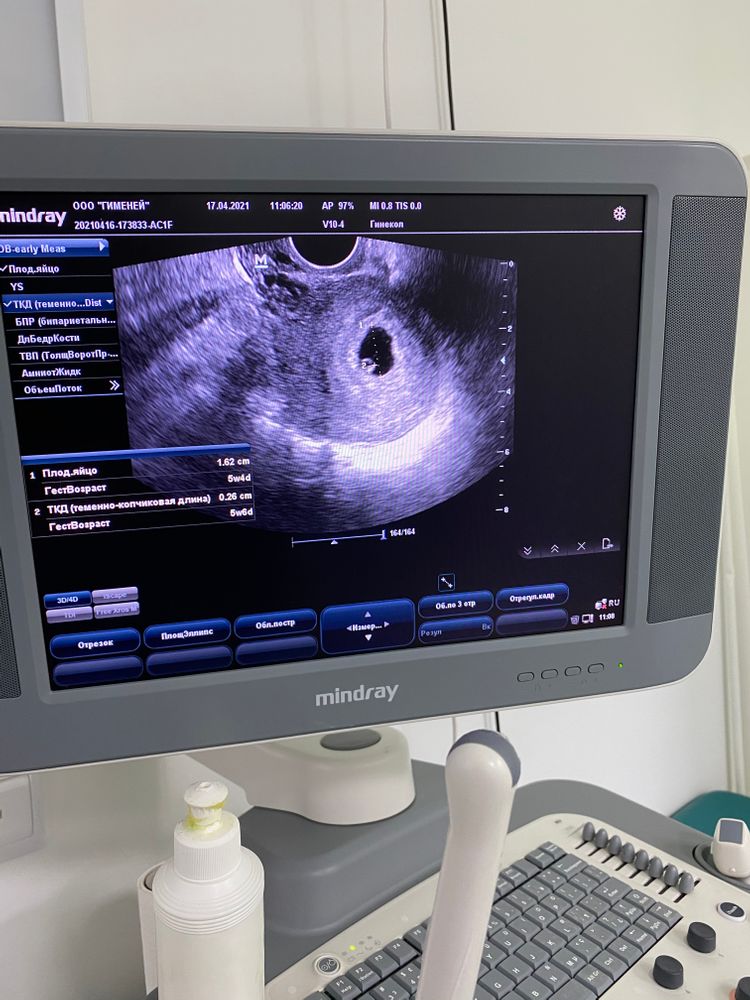

Первое узи 🥳

УЗИ, КТГ, доплерСрок по месячным 6+3

КТР 2,6 мм

СВД 16 мм

ЖМ 3 мм

сердцебиение есть

в целом сказали, что все хорошо) теперь пойду в 8 недель и там уже на учёт 🤰🏻